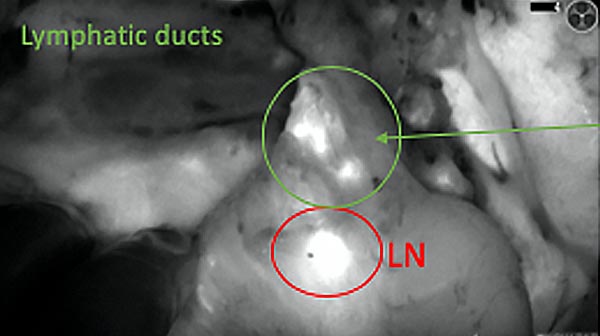

Intraoperative fluorescence imaging of the pancreas part that contains tumor

The tumor area light up fluorescently and so does a lymph node (LN; red circle) that is located on top of the tumor area. We can also see some lymphatic ducts (green circle).

After removal of the pancreas tumor fluorescence imaging was performed to check that there was no residual fluorescence left in the wound bed. A little bit of background fluorescence was found in the intestine.